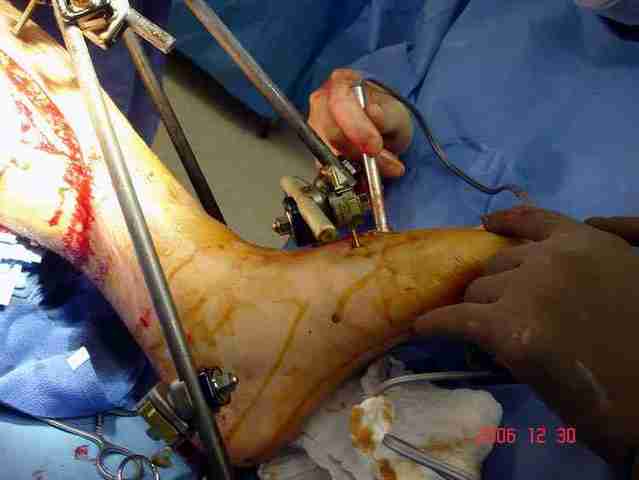

Сравнительный повторный мониторинг на компартмент синдром, на голени утром давление поднялось до 70 мм, когда послеоперационные были около 30мм.

Срочная фасциотомия на всех 4 компартментах: латерально и медиально,

кстати было достаточно только латеральной фасциотомии, чтобы услышать на допплере пульсацию,

на бедре измерения не подтвердили подозрения на компартмент синдром и рана была закрыта вакуумной губкой (wound VAC).

В настоящее время больной в реанимации по поводу Черепно Мозговой Травмы и состояние улучшается. Запланировал ушивание раны в пятницу, если позволит состояние мягких тканей и при отсутстви отека возможно удастся просунуть перкутанномедиальную пластину.